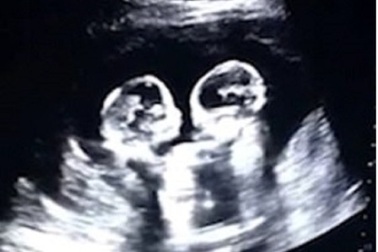

Thú vị hình ảnh chị em song sinh đánh nhau từ trong bụng mẹHai chị em sinh đôi Tao Yimo và Tao Yi’an đã trở nên nổi tiếng khắp truyền thông xã hội Trung Quốc ngay từ thời vẫn còn nằm trong bụng mẹ. Nguyên nhân bắt nguồn từ một video siêu âm thai nhi của người mẹ, cho thấy cặp sinh đôi này có “hành vi ẩu đả” rõ ràng.